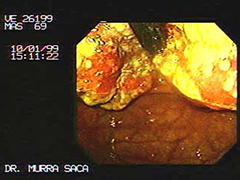

Cáncer Gástrico:

Se observa un tumor en forma de dona ulcerada que ha obstruido el antro.